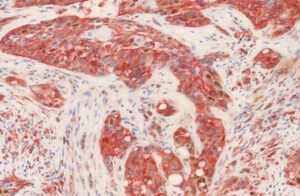

Каждая опухоль имеет свои особенности, мишени. Вид онкологического лечения, основанного на уничтожении целевых молекул (специфических генов) и ферментов, подпитывающих жизнедеятельность злокачественных клеток. Таргетная (целевая) терапия предотвращает гибель нормальных клеток и тканей, влияя только на таргетные молекулы.

Для выбора необходимого препарата врач проводит анализ на определение белковых фракций, генов новообразования.

- Ингибиторы EGFR. При раке головы и шеи может назначаться лечение, направленное на специфический опухолевый белок — рецептор эпидермального фактора роста (EGFR). Исследователи обнаружили, что препараты, которые блокируют EGFR, помогают остановить или замедлить рост некоторых видов рака головы и шеи.